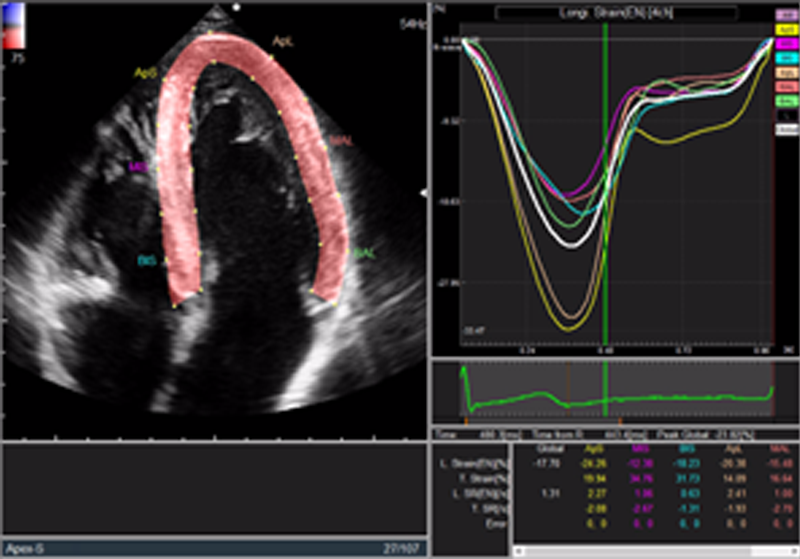

- ストレインの計測:図2の輪郭点から、それぞれ内膜ストレイン、Transverseストレインを直接計測することが可能になっている。図3は、装置上のGLS計測結果であり、輪郭線、グラフとも安定して計測されるようになった。

図3 GLS計測結果画面(GLS=-23.8%)